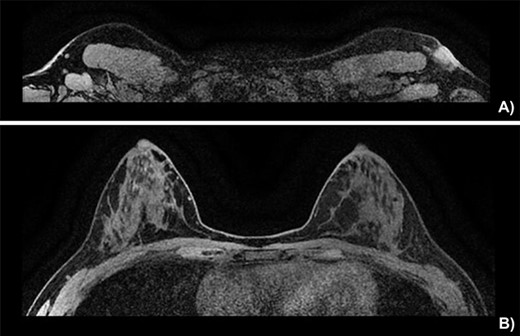

Breast MRI depicting (A) the known mass in a superficial axillary position with direct invasion of the overlying skin and dermal thickening, measured at 1.8 × 1.3 cm wide by 1.9 cm in height. The left axillary nodes appear more numerous and slightly enlarged but share no malignant features. (B) The left and right breast showing no sign of neoplasia.